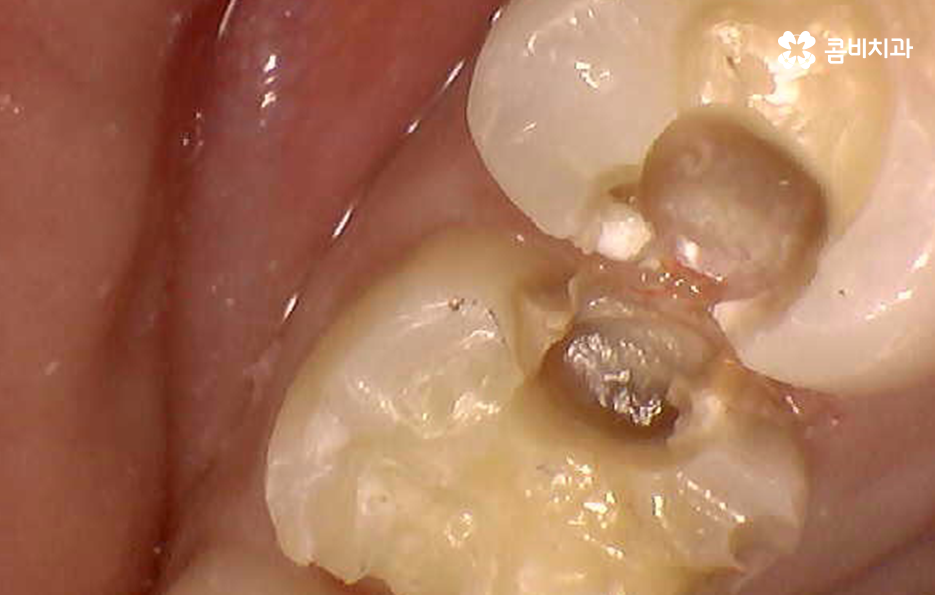

치아의 씹는면에서 발생된 충치는 치료적인 접근이 용이한 편이지만 치아 사이에 발생된 충치는 심하지 않더라도 많은 양의 치아를 삭제하여 접근해야 하는 경우가 많고 그로 인해 결국 인레이 치료를 해야 하는 경우가 많은데 치아에 발생된 충치는 보편적으로 비슷한 구강 환경에 의해 충치로 이어진 경우가 많기 때문에 단순히 하나의 치아에만 문제가 발생되어 더 문제가 커질 때까지 지켜본다는 개념보다는 구강 전체의 영향에 대해서 고려하실 필요가 있는데요

보통 치아 사이 충치 발생된 경우에는 비슷한 식습관, 생활환경, 치주질환에 의해 발생되었기 때문에 예를 들어 어금니라고 하면 주변 어금니 혹은 교합면에 해당되는 치아에도 비슷한 문제가 발생되는 사례가 많이 있어요.

치아 사이에 발생된 충치는 치아의 하단부에 발생되는 경우가 많기 때문에 신경이나 치아 뿌리 쪽에 가깝게 진행되는 경우가 많고 특히 어금니 처럼 저작력에 힘을 많이 받는 부위에 발생된 충치는 충치로 인해 치아가 약해지면서 치아가 깨지면서 문제가 드러나는 경우도 있기 때문에 치아의 파절로 까지 이어지는 경우도 있으므로 늦지 않게 치료하시길 권하고 있어요